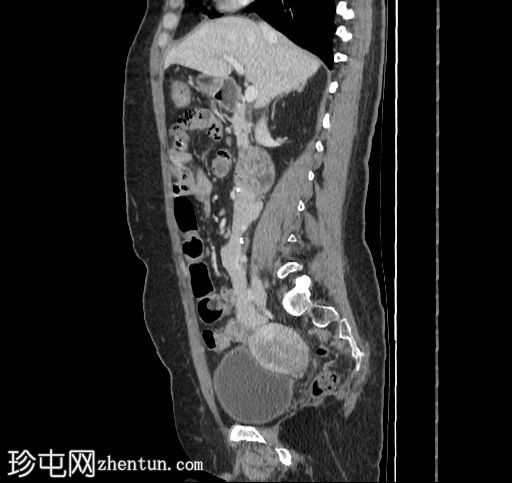

轴位增强扫描

动脉期

移植的胰腺位于右侧腹膜后间隙,大小和形态(轴位、冠状位和矢状位)均正常,可见相关手术缝合线。供体十二指肠段与自体十二指肠吻合。可见胰腺移植物与右髂血管的动脉吻合,胰腺实质强化均匀,提示移植物灌注良好。

左髂窝肾移植(轴位、冠状位),显示移植肾与同侧髂总血管的动脉和静脉吻合。移植肾形态完整,实质均匀强化。

本例中,影像学检查显示原位肾脏和胰腺明显萎缩,符合长期糖尿病合并慢性肾脏病的表现。肾移植位于左髂窝,与同侧髂血管的动脉和静脉吻合通畅,肾实质均匀强化,这些影像学表现均符合功能性肾移植的影像学特征。移植胰腺位于右侧腹膜后,形态和位置均符合原位胰腺,供体十二指肠袢与原位十二指肠吻合良好。